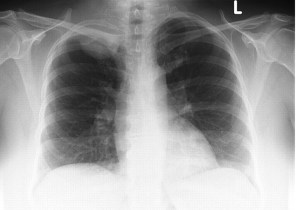

341) A 78 year old man presents with progressively increasing shortness of breath. He has a 100 pack year history of smoking. His past medical history is significant for chronic obstructive pulmonary disease, coronary artery disease and congestive heart failure. He has been admitted several times in the past one year for Congestive heart failure exacerbations which resulted from his non-compliance with diet and medications. His medications include aspirin, metoprolol, enalapril, and spironolactone and tiotropium inhaler. On examination, he is afebrile with respiratory rate 24/min, pulse 106beats/min, blood pressure 140/90. Breath sounds are decreased and there is dullness to percussion on the left side of the chest. Heart sounds are regular and there is no S3 gallop. A 2D echocardiogram reveals ejection fraction at 30% and a brain natriuretic peptide 250 pg/ml (Normal less than 100pg/ml) . An EKG reveals changes consistent with left ventricular hypertrophy. A Chest X-ray is shown below:

Which of the following is the most appropriate next step in management?

A) Intravenous Furosemide

B) Tube Thoracostomy

C) Intravenos Nitroglycerin

D) Needle thoracentesis

E) Implantable Cardioverter-Defibrillator (ICD) placement